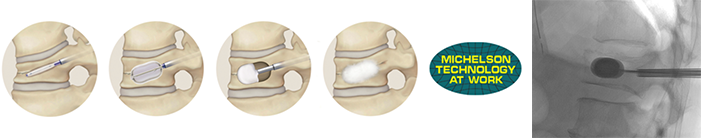

BKP(Balloon Kyphoplasty:経皮的椎体形成術)

骨粗鬆症などで生じる圧迫骨折は多くが保存的に治療されますが、痛みが続く場合には BKP が適応となります。約5mmの小切開から針を挿入し、風船で空間を作った後に骨セメントを注入して椎体を安定化します。出血が少ない低侵襲手術で、術後すぐに痛みが軽減するのが特徴です。骨粗鬆症性骨折だけでなく、転移性脊椎腫瘍による骨折にも有効です。